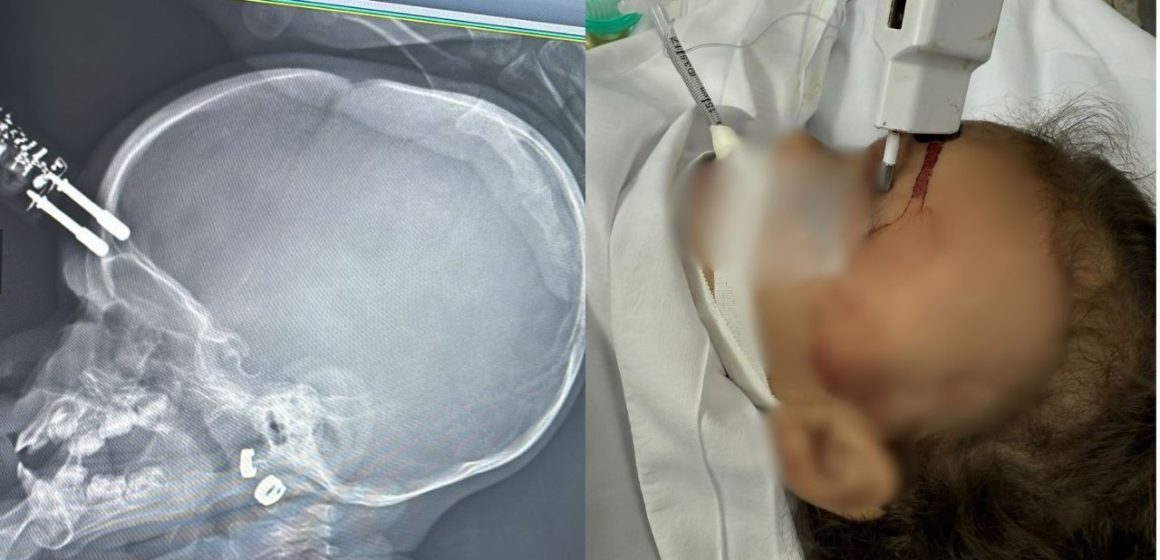

A hipótese mais provável para o acidente é que a menina estivesse segurando o carregador no momento da queda. O objeto, com suas pontas metálicas, perfurou a região frontal da cabeça da criança, perigosamente próxima à área ocular. Dr. Bruno Castro enfatizou a gravidade potencial do incidente, mencionando que um impacto direto no olho poderia ter resultado em perda permanente da visão, destacando a sorte na localização da lesão.

Imediatamente após o incidente, a menina foi submetida a uma cirurgia de emergência no Complexo de Saúde São João de Deus. Durante o procedimento, a equipe médica conseguiu remover o carregador com sucesso e realizou a reconstrução da área afetada. A agilidade no atendimento médico foi fundamental para evitar complicações severas, como hemorragias extensas, infecções e o risco de meningite, uma inflamação grave das membranas que envolvem o cérebro e a medula espinhal.